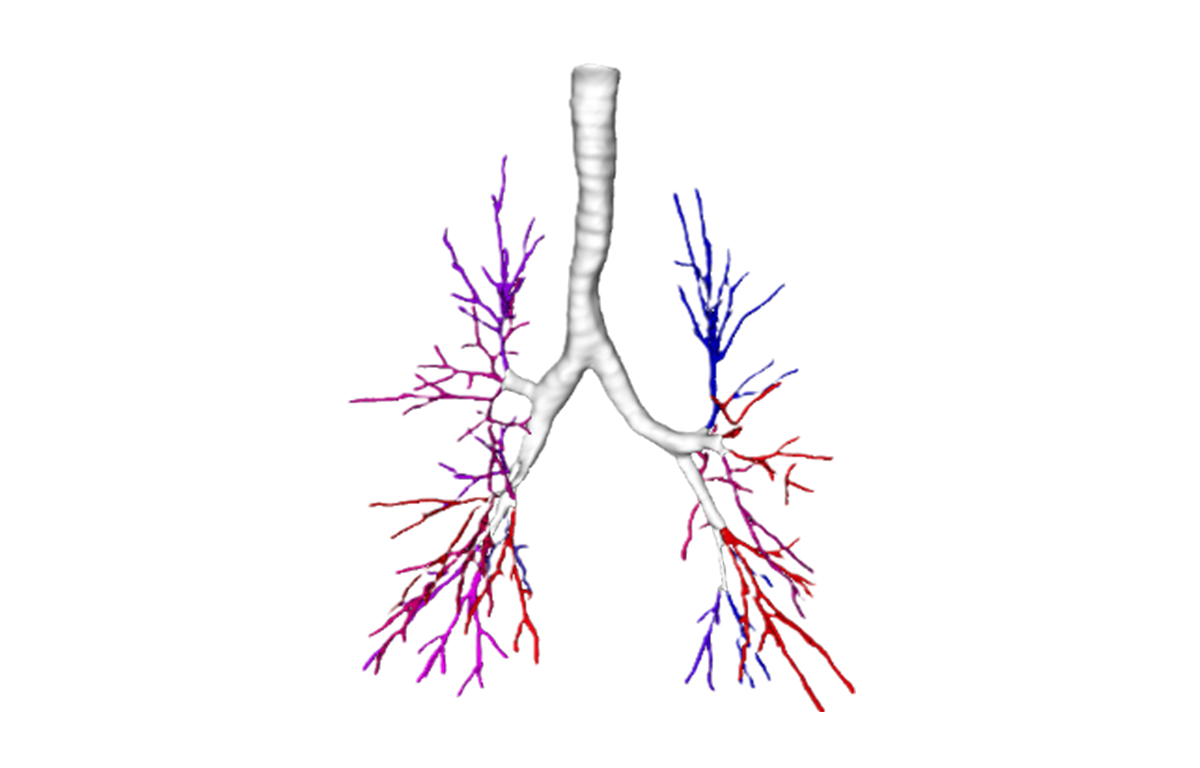

Built on advanced capabilities in lung segmentation and quantification, our AI technology interprets thoracic CT data with anatomical precision - capturing airway trees, parenchymal patterns, and vascular structures, even in severely diseased lungs.

Examples of core capabilities that provide complementary detailed, procedure-relevant insights include:

- Segmentation of anatomical structures up to sub-segmental level

- Anatomical mapping to support navigation planning and guidance